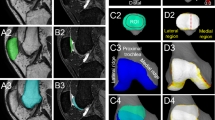

OD was discerned through MRI, and categorized as either damage osteochondral (labeled as “D”) or a normal osteochondral (labeled as “N”). The regions affected by OD were delineated into the lateral femoral condyle (LFC) and medial patella (MP). Manifestations of osteochondral damage encompassed partial-thickness chondral defects (< 100% of the articular cartilage thickness), full-thickness chondral defects (involving intact subchondral bone), osteochondral lesions (involving an underlying cortical defect), and avulsion fractures17,18. Examples are depicted in Fig. 1.

Sagittal and axial images were employed for the assessment of PF morphology. To analyze the geometry of the articulating joint, angles and distances were gauged up to the furthest cartilaginous point. Measurements of parameters including the Caton-Deschamps index (CDI)19, tibial tuberosity-trochlear groove distance (TT-TG)20, patellar width and thickness16, medial and lateral trochlear facet length21, patellar inclination angle (LTI)22, and sulcus angle23 were executed following established protocols in the literature. The anatomical epicondylar axis (AEA), a reliable reference on the distal femur, facilitated the measurement of femoral condyle and trochlea morphology in the transverse plane24. The femoral condyle was partitioned into four quadrants for a more comprehensive evaluation of the correlation between PF geometry and OD. The vertical distance from the highest point of the condylar cortex to the AEA was measured to determine the lengths of the anterior and posterior condyles. Examples are depicted in Fig. 2.

Morphological measurements of the trochlear and patellar regions were conducted as follows: (A) TT-TG measurement; (B) condylar length measurement in the following regions: (a) anteromedial condyle, (b) posteromedial condyle, (c) anterolateral condyle, (d) posterolateral condyle; (C) Measurement of medial and lateral trochlear facet lengths; (D) sulcus angle measurement; (E) LTI measurement; (F) patellar width and thickness measurement.